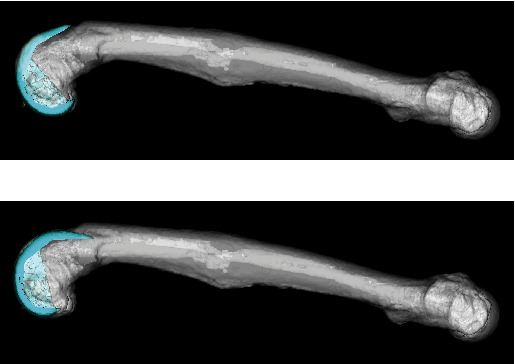

Background: Knee osteoarthritis (OA) with extra-articular deformity (EAD) is a rare condition for which achieving accurate alignment with total knee arthroplasty (TKA) is difficult. Extra-articular corrective osteotomy may be necessary for severe deformities. Case Presentation: A 76-year-old man underwent TKA for knee OA with EAD due to malunion after fractures of the femur and tibia. The femoral varus and the tibial valgus/recurvatum deformities were mild and corrected by intra-articular osteotomy using navigation (i.e., navigation-assisted standard TKA). However, the femoral antecurvatum deformity was severe, and we performed extra-articular corrective osteotomy simultaneously with TKA. Navigation was used not only for TKA but also for extra-articular corrective osteotomies. The osteotomy site was fixed with a cemented stem and metaphyseal sleeve. The postoperative hip-knee-ankle angle was 1° varus, the femoral implant was implanted at 0.5° varus/0.5° flexion, and the tibial implant was implanted at 0.5° varus/0° posterior slope. Two years after surgery, improvements were obtained in the range of motion from 15°-95° to 0°-110°, the Knee Society Score from 39 to 92 points, and the functional score from 35 to 100 points. Conclusions: One-stage TKA with extra-articular corrective osteotomy achieved good clinical results due to accurate alignment using navigation and firm fixation of the osteotomy site using cemented-stem and metaphyseal sleeve without any fixation devices.

Abstract Image